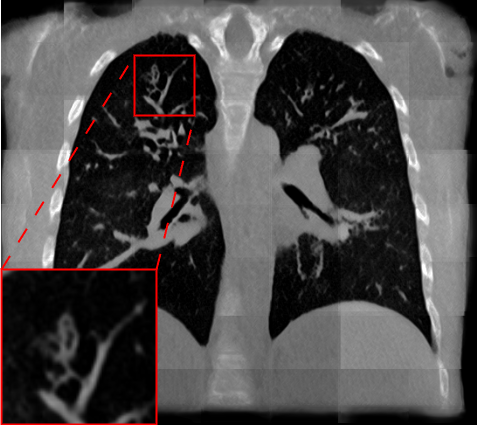

Fig. 2 presents a visual comparison of lung coronal sections from different models. The model using L1 loss results in blurred images, with particularly poor bone reconstruction. In contrast, the MedicalNet-based model produces sharper images but introduces artifacts in anatomical areas. Models based on AFP loss offer visually appealing results, with well-reconstructed anatomical bones and lung tissue. Additionally, only NaviAirway and HAL methods provide detailed bronchial reconstruction, as highlighted in the zoomed-in section.

To handle memory constraints during training and inference, we used a patch-based strategy. We experimented with multiple patch sizes, including and , and also used nnU-Net’s default adaptive windowing strategy (e.g. for thoracic cases). While larger patches provide more contextual information and generally improve reconstruction quality, the overall performance did not differ substantially from nnU-Net’s dynamic patching. Some visible artifacts in Fig.2 result from patch combination, especially in regions not covered by the segmentation network used for AFP supervision. For instance, when the AFP loss relies on the NaviAirway model, artifacts often appear outside the lung fields, as the network lacks anatomical guidance in those regions. However, these artifacts are purely visual and do not affect the downstream segmentation results or the quantitative metrics reported, which are detailed in the upcoming paragraph.

Table 1 presents a quantitative evaluation of the model’s performance on lung MR to CT synthesis, based on the MAE, SSIM, Dice score, and NSD between synthesized and ground truth CT images. The adapted nnU-Net trained with L1 loss delivers the best performance on intensity-based metrics, yielding a MAE of 48.72 and an SSIM of 0.837. In contrast, other models based on perceptual loss or AFP loss achieve average MAE results but maintain competitive SSIM values, for example, the AFP loss with TotalSegmentator embeddings achieves an SSIM of 0.828. In the context of airway segmentations using the NaviAirway pipeline, the adapted nnU-Net models with AFP loss from NaviAirway and HAL’s embeddings deliver the best performance, achieving the highest Dice score of 0.584 and NSD value of 0.723. Conversely, models employing L1, perceptual, or AFP loss with TotalSegmentator’s embeddings yield poorer results, lacking precise bronchial reconstruction. The GAN-based SPADE method generally underperforms compared to nnU-Net, but adding AFP loss to SPADE enhances its performance. These metrics align with qualitative analysis from Fig. 2 and Fig. 3, with the models using AFP loss delivering the best performance in airway reconstruction.